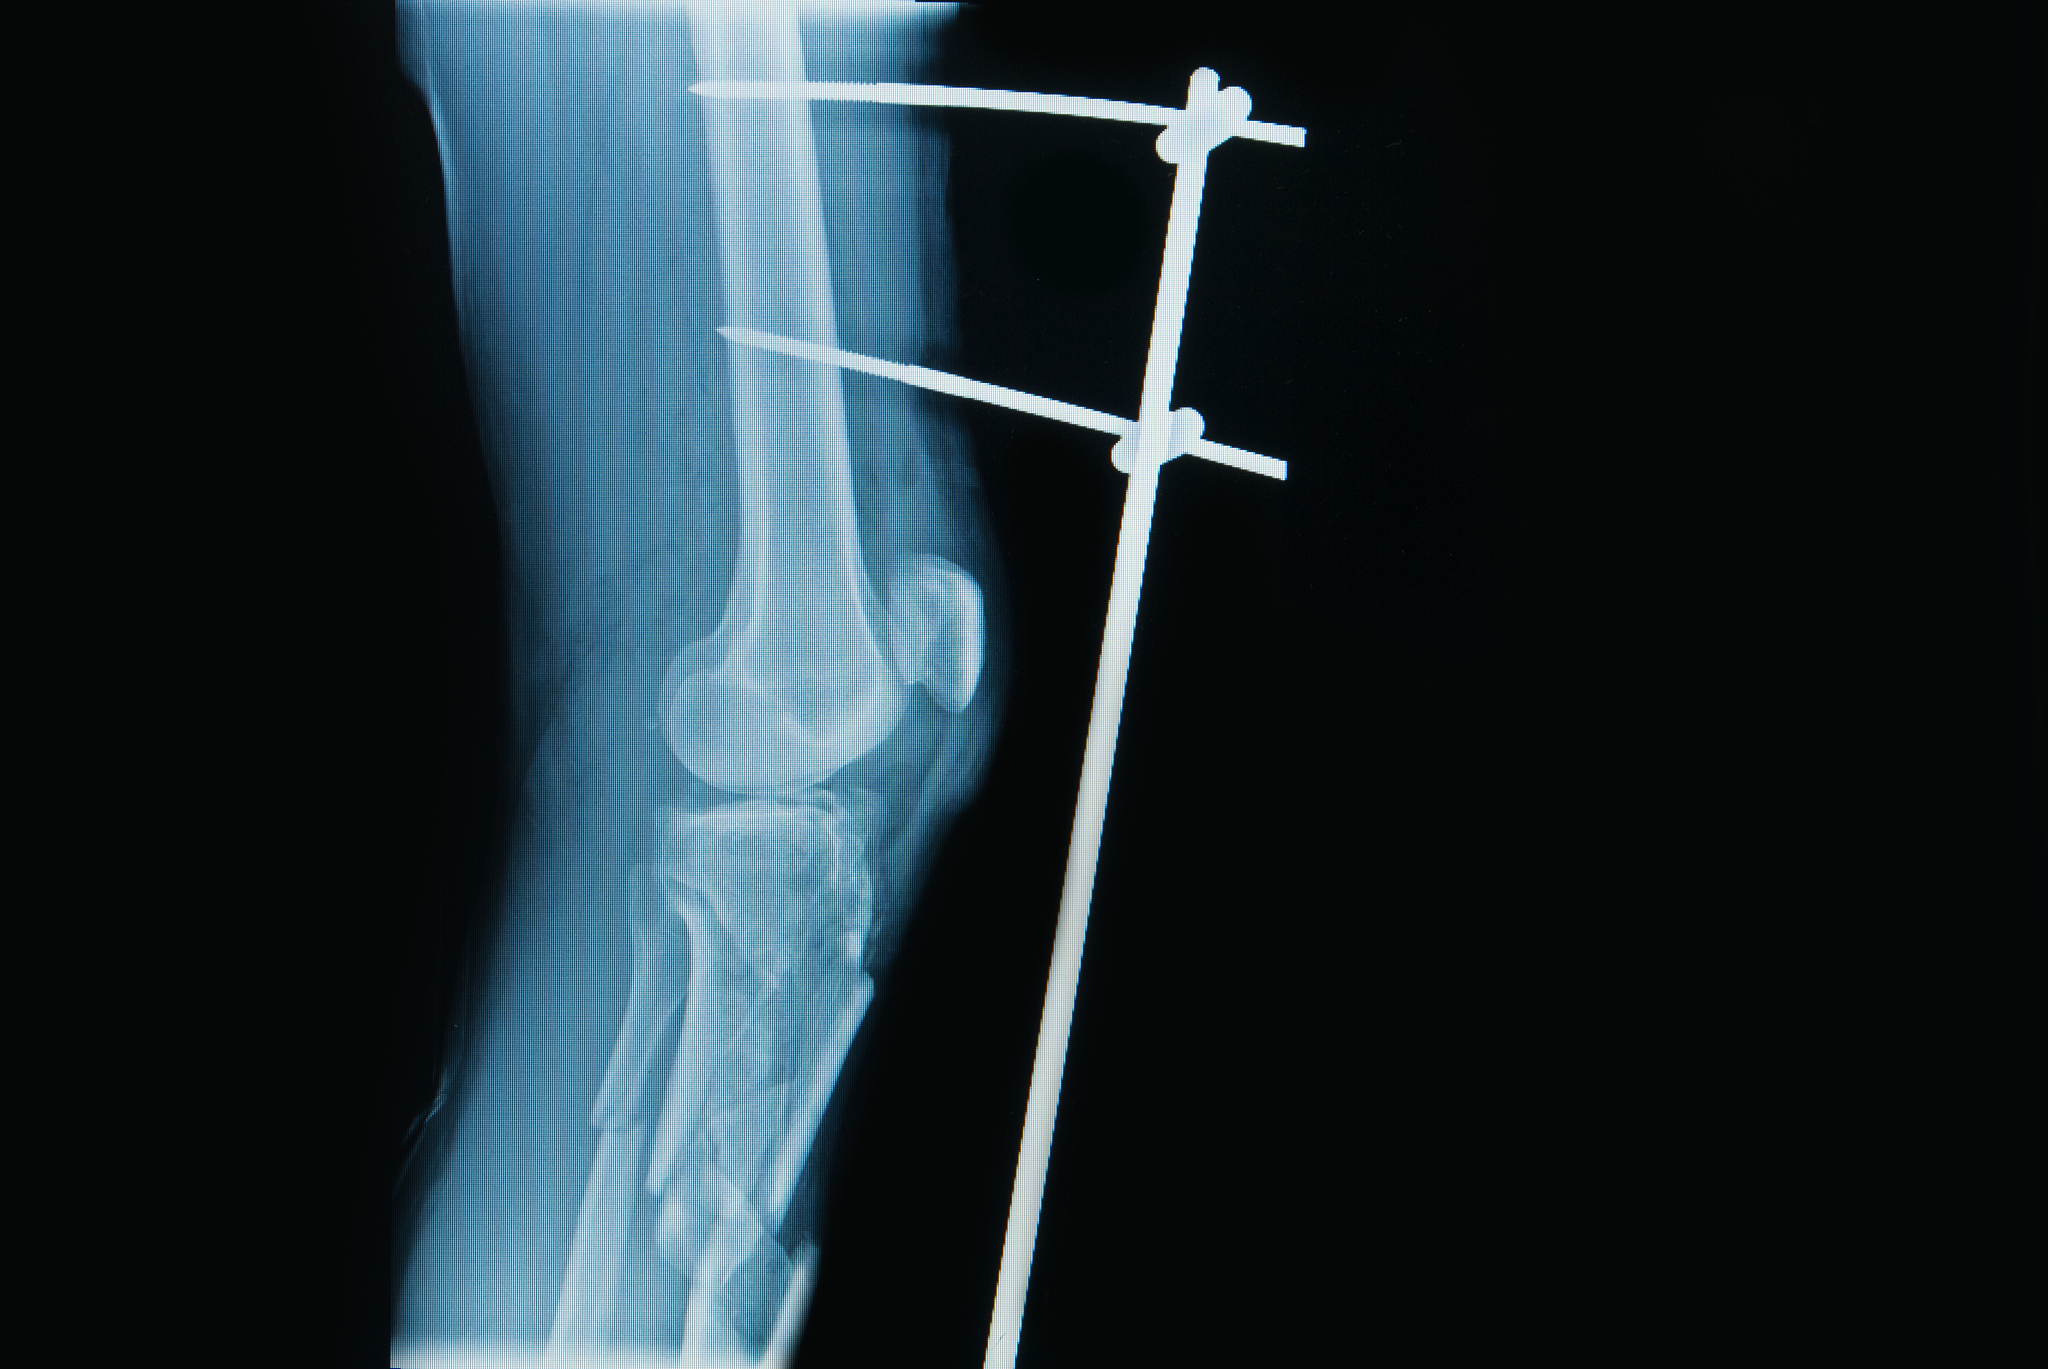

在腰硬联合麻醉下进行右胫骨平台粉碎性骨折切开复位内固定+前交叉韧带止点撕脱修补术的具体措施包括以下步骤:

4. 内固定:使用金属板、螺钉或钢钉等内固定物将骨折碎片固定在正确的位置上,以促进骨折的愈合。

在腰硬联合麻醉下行右胫骨平台粉碎性骨折切开复位内固定+前交叉韧带止点撕脱修补术治疗具体措施